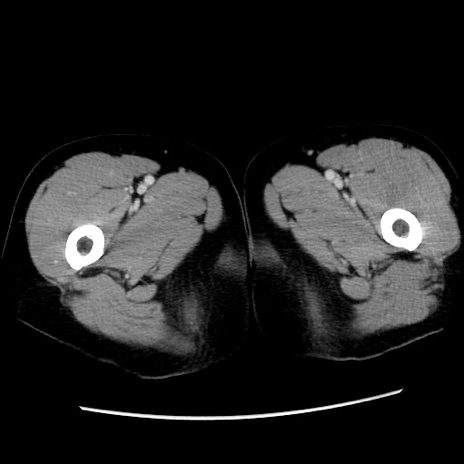

症例10(横断像)

【症例】 50歳代女性

【主訴】 腹痛

【現病歴】前日生レバーを食べた。今朝に排便あり。 昼前に突然発症の腹痛を生じ、当院救急外来を受診した。

【既往歴】 子宮筋腫にてで子宮全摘後

【身体所見】 意識清明、腹部:平坦、軟、下腹部やや左を中心に圧痛・反跳痛あり、筋性防御あり

【データ】WBC 7800、CRP 0.07